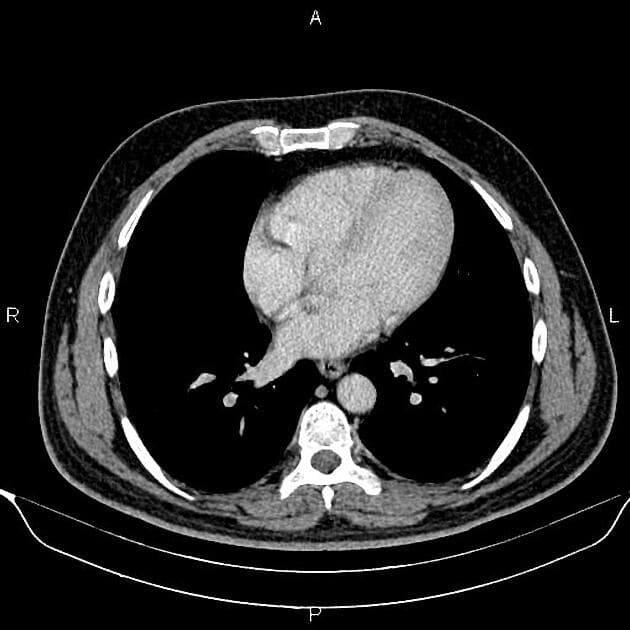

- Một khối nang khu trú một phần lồi ra ngoài (exophytic) kích thước 48 mm, thành dày ngấm thuốc (enhancement) và có các vách ngăn cùng các nốt ngấm thuốc lệch tâm (eccentric enhancing nodules) được ghi nhận ở phần giữa của thận phải.

- Một vài mạch máu tuần hoàn bàng hệ (collateral circulation) nhỏ giãn được ghi nhận trong khoảng gian thận (perinephric space).

- Ngoài ra, thấy một vài nang đơn thuần (simple cortical cysts) ở vỏ thận hai bên.

Khối nang thận - phân loại Bosniak IV (Renal cystic mass - Bosniak class IV)

- "Các đặc điểm hình ảnh chính bao gồm thành dày ngấm thuốc, vách ngăn ngấm thuốc và các nốt ngấm thuốc lệch tâm."